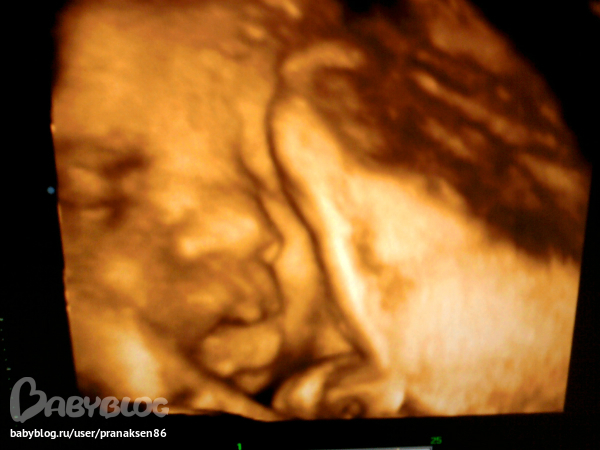

До этого была совсем низко - 2.2 см от внутреннего зева. Малыш перевернулся и теперь в головном предлежании!! Я на 7ом небе от счастья!! Голова сказали у нас большая.. 9 см почти. Смотрели в 3D нас, такие холёёёсие ))) Сделали несколько фото личика ) По этому УЗИ срок 9 января :) все раньше и раньше

И напоследок наше личико крупным планом. Нос, губки и щёчки мои, а брови мужа )))